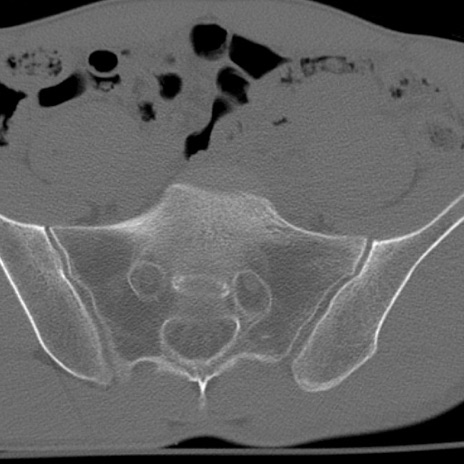

症例3 腰椎CT(横断像)

腰椎CT